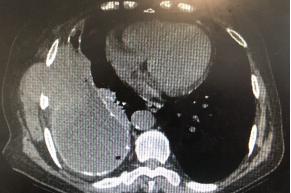

CT引导下胸腔积液置管引流

针对局限少量的包裹性积液,常规超声定位不能进行胸腔穿刺时,CT引导下放置引流管引流胸水是一种安全的微创技术,不仅可以采集胸水用于诊断,还可以同步进行胸膜穿刺活检获取胸膜组织进行诊断,放置引流管后还可以注射尿激酶、组织相容性纤溶酶原等药物进行相关治疗。